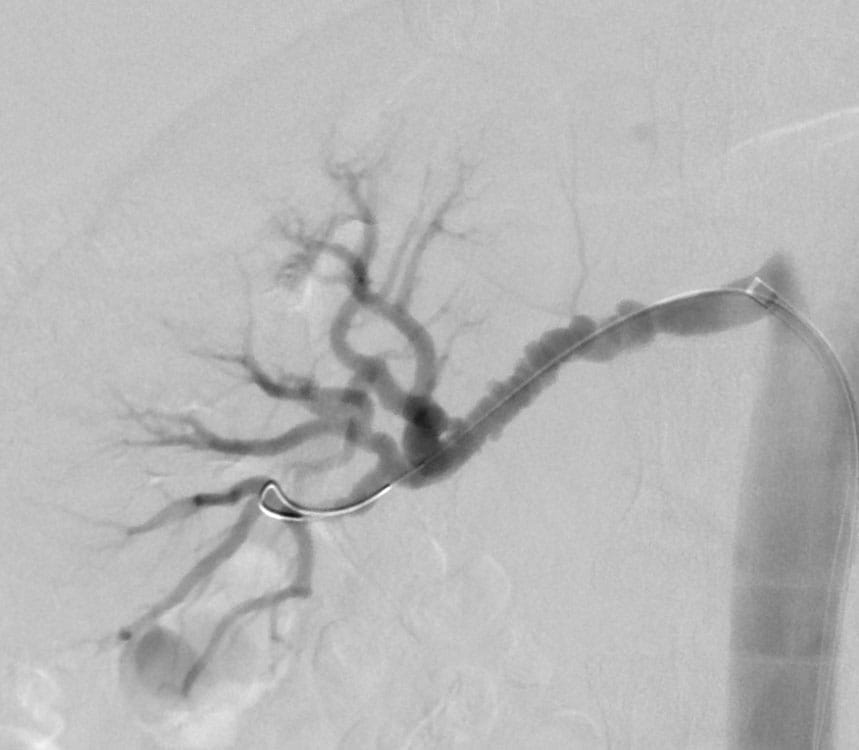

Patients coping with fibromuscular dysplasia (FMD), a non-atherosclerotic disease of the arterial walls, will be invited to participate in the biobank to advance understanding of this idiopathic disease.

“Fibromuscular dysplasia is a rare vascular disease that can have a major impact on patients’ health and quality of life,” says Heather Gornik, MD, a world-renowned expert in FMD who is Co-Director of the Vascular Center and Director of the Fibromuscular Dysplasia and Arterial Dissection Program at UH Harrington Heart & Vascular Institute, and Professor of Medicine at the School of Medicine.